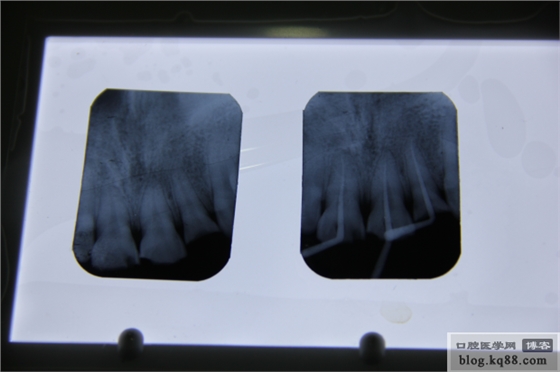

首先拍張片子吧

片子顯示牙根沒有折斷。右上2已漏髓,兩個1也有出血點(diǎn)。建議根管治療,待烤瓷修復(fù)。局麻下開髓,測量根管長度,機(jī)括至大錐度F2.次氯酸鈉加鹽水大量沖洗。預(yù)備完成,看看試尖片。

感覺還可以,說明宇森的根測測量的很準(zhǔn)。再看看根充以后的片子。

發(fā)現(xiàn)一個不該犯得的錯誤,髓室居然沒有完全打開。再看看從始至終的片子吧!